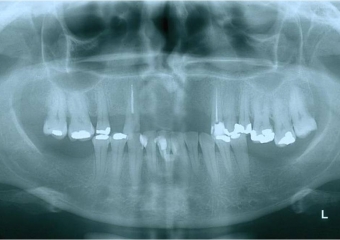

Raio x inicial